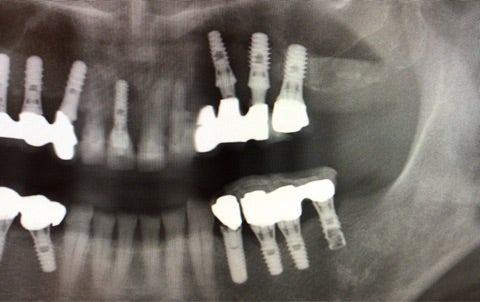

『昔通っていた歯科で埋入したインプラントの周りに違和感があり、最近になってグラグラしてきている』

▶︎赤いラインで引いた部分までインプラントの周りの骨が吸収していることがわかります。